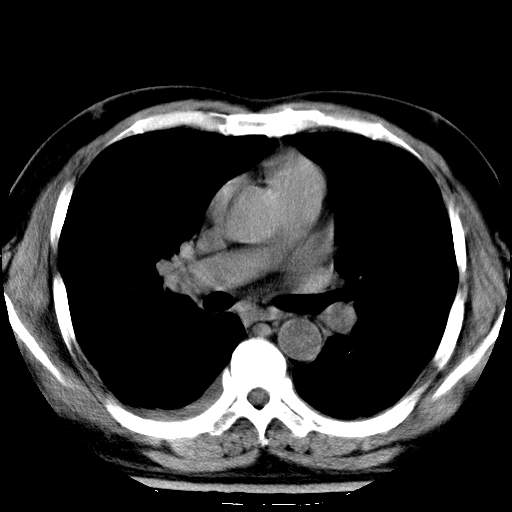

标题: CT21804:男,65岁,咳嗽、咳痰、发热5天。 [打印本页]

男,65岁,咳嗽、咳痰、发热5天。

慢支,肺心病

支持慢性支气管炎伴感染,双侧少量胸腔积液.

两肺间质纤维化,支扩合并感染,双侧胸腔积液

慢性支气管炎并感染,支扩,双侧少量胸腔积液.